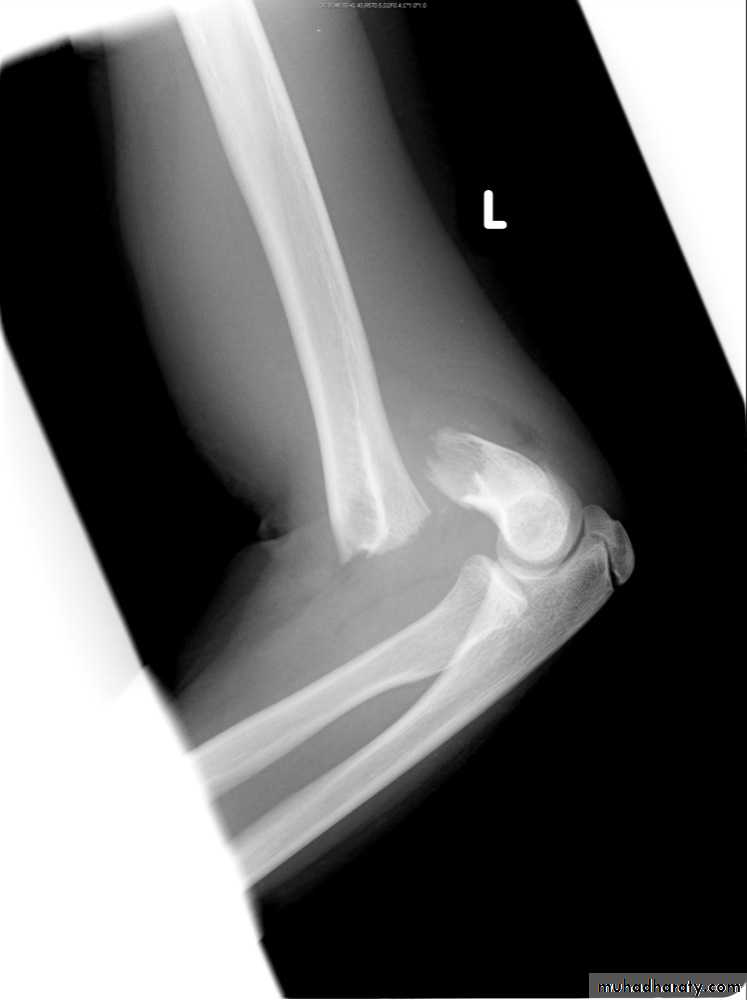

Slide 5 2 days post fall from a height1- What we call this sign?2- What does it indicate?